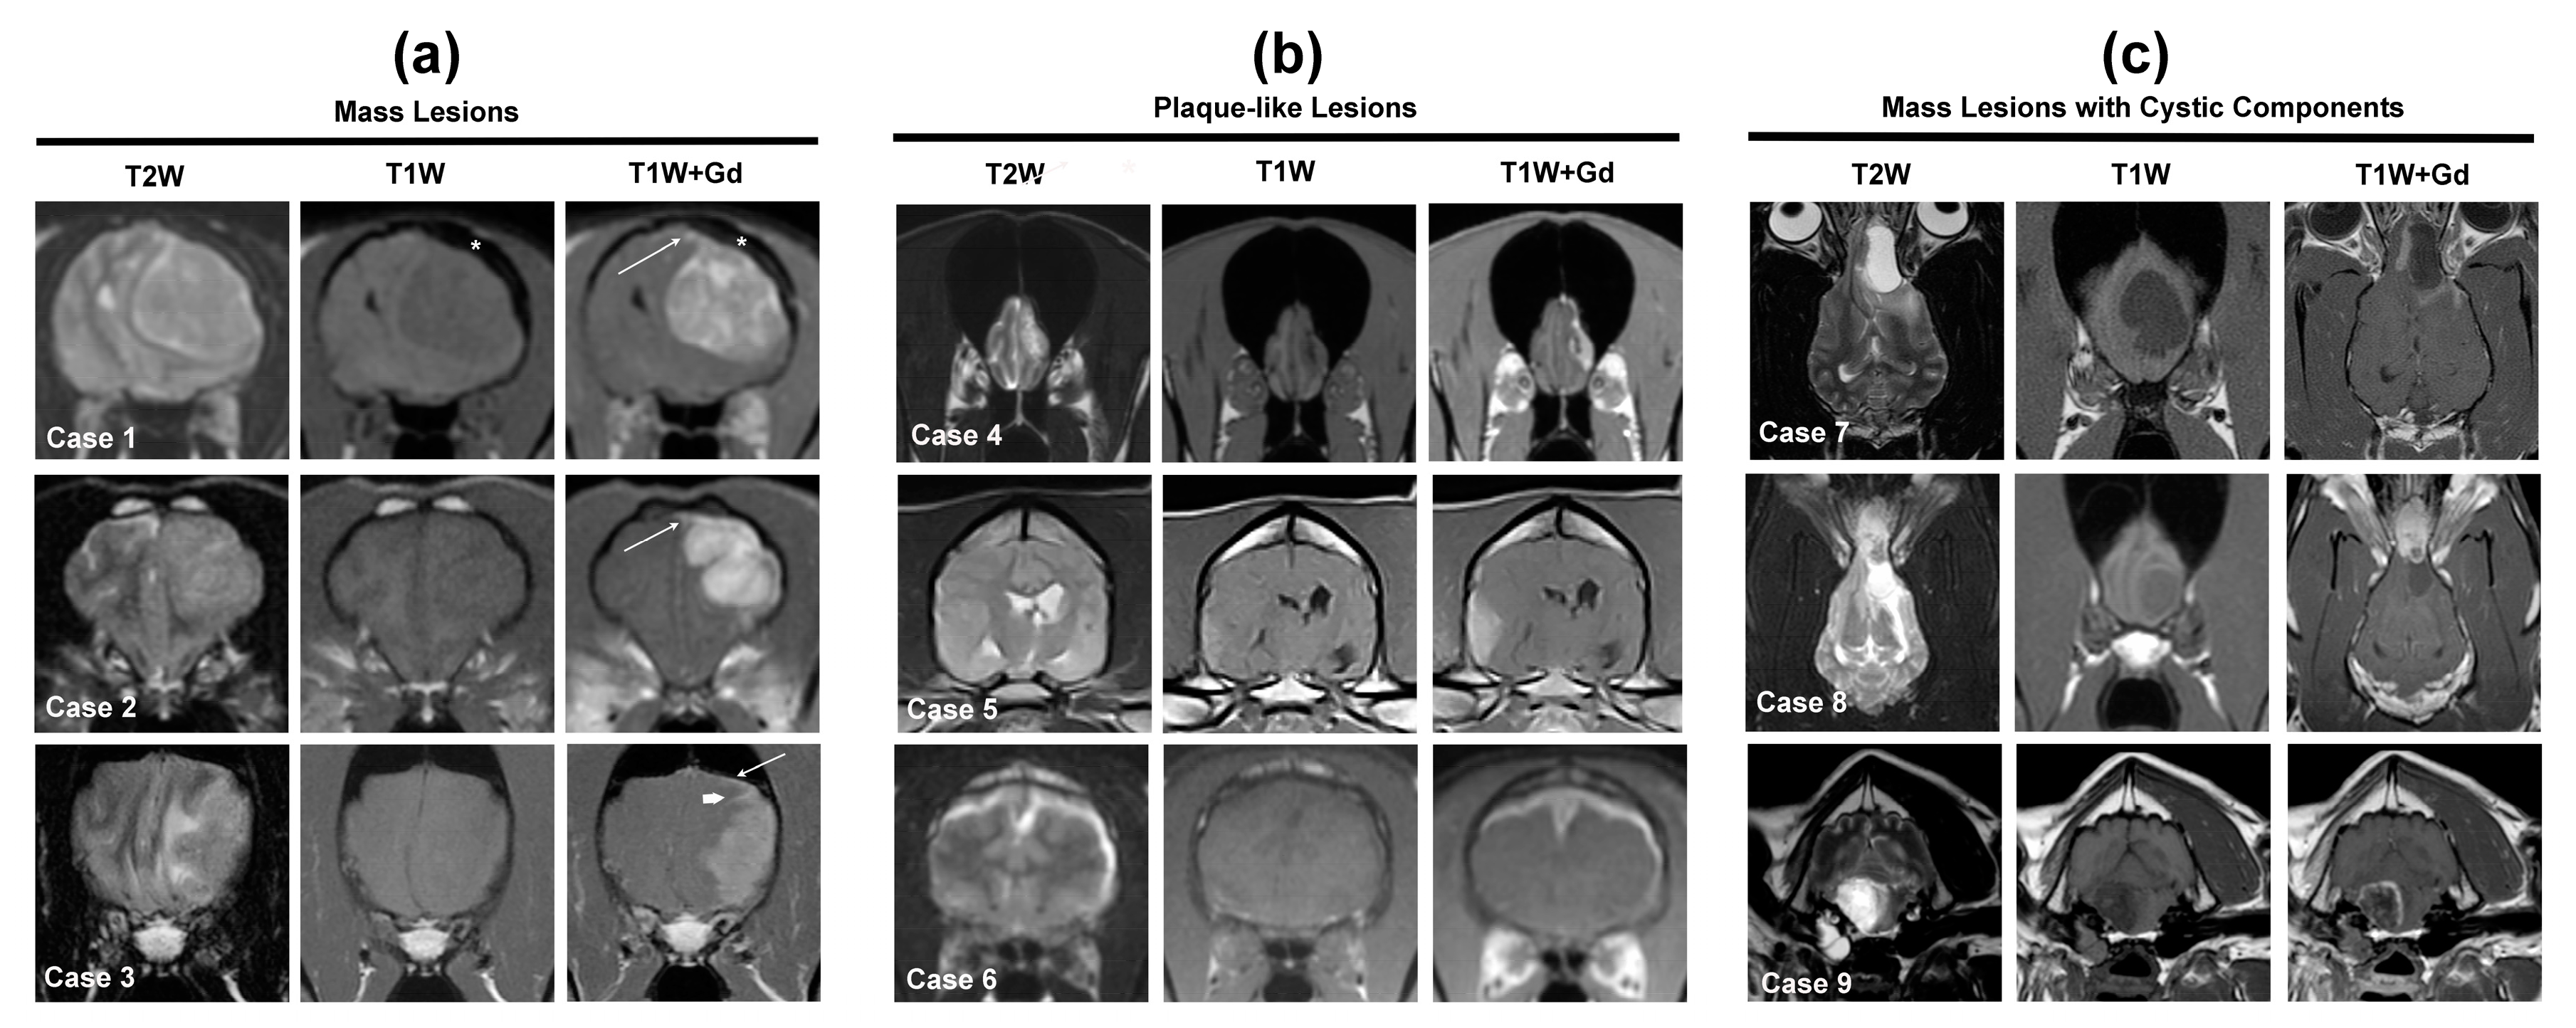

Figure 3.

MRI features of solitary, extra-axial, meningeal-based neoplastic lesions in dogs and cats. Cases 1–3 (a) illustrate mass lesions, Cases 4–6 (b) are plaque-like lesions, and Cases 7–9 (c) are mass lesions with significant cystic components. Case 1—feline Grade I cerebral convexity meningioma. The tumor is broad-based and well-demarcated, associated with mass effect manifested as a falx shift and compression of the left lateral ventricle, and is T2W iso- to-hyperintense, T1W hypointense, and markedly and heterogeneously contrast enhancing. Note the dural tail sign (arrow) and calvarial hyperostosis (*). Case 2—canine Grade II cerebral convexity meningioma with similar signal appearances as in Case 1, with dural tail sign (arrow). Case 3—canine intracranial histiocytic sarcoma. The tumor is T2W iso- to hyperintense, T1W iso- to hypointense, uniformly contrast enhancing, and has a dural tail feature (arrow) with an extension of contrast enhancement into the leptomeninges of the sulci (arrowhead) and associated mass effect and perilesional T2W hyperintensity representing edema. Case 4—canine Grade I plaque-like cerebral convexity meningioma. Case 5—canine granular cell tumor appears as a plaque-like lesion that is iso-to hyperintense on T2W images, T1W hyperintense, markedly contrast enhancing, and associated with mass effect. Case 6—feline intracranial B-cell lymphoma manifesting as marked T2W hyperintense, T1W hypointense, markedly contrast-enhancing, and plaque-like thickening of the pachymeninges of both cerebral hemispheres. Case 7—canine Grade I cystic olfactory meningioma. The mass is well demarcated, with cystic regions represented by areas of marked and uniform T2W hyperintensity and T1W hypointensity. Solid portions of the tumor are contrast-enhancing and surround the cystic region. Perilesional T2W hyperintensity represents edema in the caudal aspect of the mass. Case 8—canine olfactory neuroblastoma, which shares imaging features with cystic meningiomas. The mass is heterogeneously T2W hyperintense, with the caudal cystic aspect of the mass being markedly hyperintense, T1W iso- to hypointense, and the rostral portion of the tumor demonstrates marked but heterogenous contrast enhancement. Note the solid, enhancing portion of the mass extending from the nasal cavity through the cribriform plate into the calvarium and the extensive perilesional T2W hyperintensity (edema) extending caudally along the subcortical white matter tracts. Case 9—canine Grade I microcystic meningioma of the cerebellopontine angle. Intratumoral cysts account for the T1W and T2W signal heterogeneity, and the mass demonstrates peripheral ring-type enhancement. Note the presence of fluid material in the middle ear as well as the marked neurogenic atrophy of the muscles of mastication ipsilateral to the tumor.

The reported MRI signal intensities of canine and feline meningiomas are variable (Table 1) and not specific for any particular extra-axial meningeal-based tumor or non-neoplastic lesion [7,11]. The majority of canine and feline meningiomas are isointense to hypointense on T1W images and heterogeneously hyperintense on T2W/FLAIR images [9,10,30,31,32,48,49]. Although contrast-enhancement occurs nearly universally in canine and feline meningiomas (Table 1), studies report considerable variability as to whether contrast-enhancement occurs homo- or heterogeneously (Table 1), as well as a wide range of the incidence of the dural tail sign in canine meningiomas [9,10,30,31,32,39,48,49]. The majority of meningiomas display well-demarcated borders, particularly on T1W+Gd images (Figure 3, Cases 1, 2, 4, 7, 8), and a sharply defined border has been shown to be predictive for the presence of a neoplastic rather than inflammatory or vascular lesions on MRI studies [7].

Meningiomas are also the primary diagnostic consideration for extra-axial meningeal-based lesions that contain large solitary or multifocal cysts (Figure 3, Cases 7–9), which appear as well-demarcated T1W hypointense, T2W hyperintense, non-enhancing spherical to multiloculated regions [47,48]. Cystic meningiomas have comprised 13–32% of canine meningiomas included in the studies in this review [2,7,10,30,31,32,40,48,52,53,54], although an additional subset of meningiomas also contain smaller foci of intratumoral cysts/fluid or intratumoral hemorrhage, with hemorrhage appearing as conspicuous signal voids or susceptibility artifacts on T2*GRE or SWI [9,14,48,54].

Meningiomas are frequently associated with secondary changes in the brain (Table 1), such as peritumoral edema and mass effect [2,9,41,48]. Peritumoral edema, which is T1W hypointense and T2W/FLAIR hyperintense, is predominantly vasogenic with a propensity to track along white matter tracts adjacent to the tumor. Peritumoral edema is often subjectively defined as mild, moderate, and severe, with most sources considering edema involving ≥3 cerebral lobes or an entire hemisphere to be severe [2,10,31,32]. Mass effect can manifest in many forms, including effacement of sulci, shifting of midline structures, compression of ventricles, or the presence of brain herniations [12,13,14,41]. Cats with meningiomas frequently have brain herniations on MRI, with a reported incidence of 63–100%, which is likely attributable to the relatively high tumor volume present in most cats at the time of diagnosis [9,41]. Brain herniations in dogs with meningiomas also occur commonly, although the incidence is highly variable, as this imaging feature of mass effect is not always specifically reported [41]. Canine meningiomas have also been shown to cause displacement of local blood vessels in three dimensional time-of-flight magnetic resonance angiographic (3D TOF MRA) studies [53]. Meningiomas are also the most likely extra-axial, meningeal-based tumors to cause secondary changes in the skull adjacent to the tumor [9,40,52]. Bony changes most often consist of thickening and sclerosis of the calvarium (calvarial hyperostosis) but can also rarely include lysis [2,9,40,52]. Calvarial hyperostosis (Table 1; Figure 3, Case 1) is observed much more frequently in feline meningiomas [9,40,52].